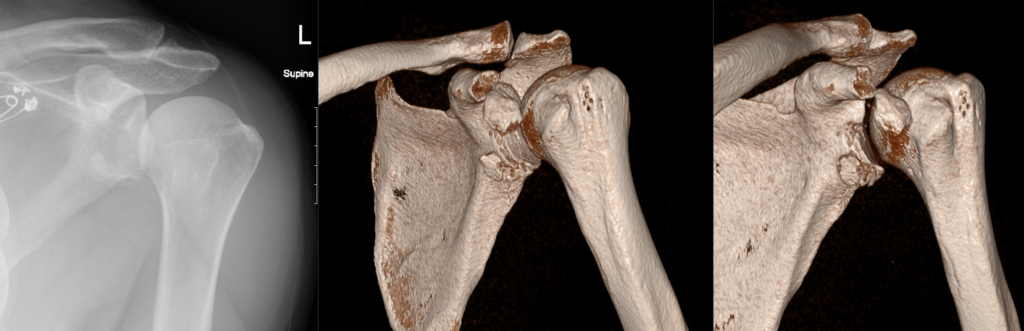

CT Case 104

A 45 year old female presents with shoulder pain following a seizure.

An X-ray of the shoulder found an enlocated shoulder with an irregularity around the glenoid rim.

A CT of the left shoulder is arranged.

Describe and interpret the CT scan

1. Hill-Sachs deformity in the posterior aspect of the humerus.

2. Comminuted displaced osseous (bony) Bankart lesion involving the anterio-inferior glenoid fossa (6-10 o’clock).

3. Comminuted laterally displaced fracture of the coracoid process.

4. Associated joint effusion and surrounding soft tissue haematoma.